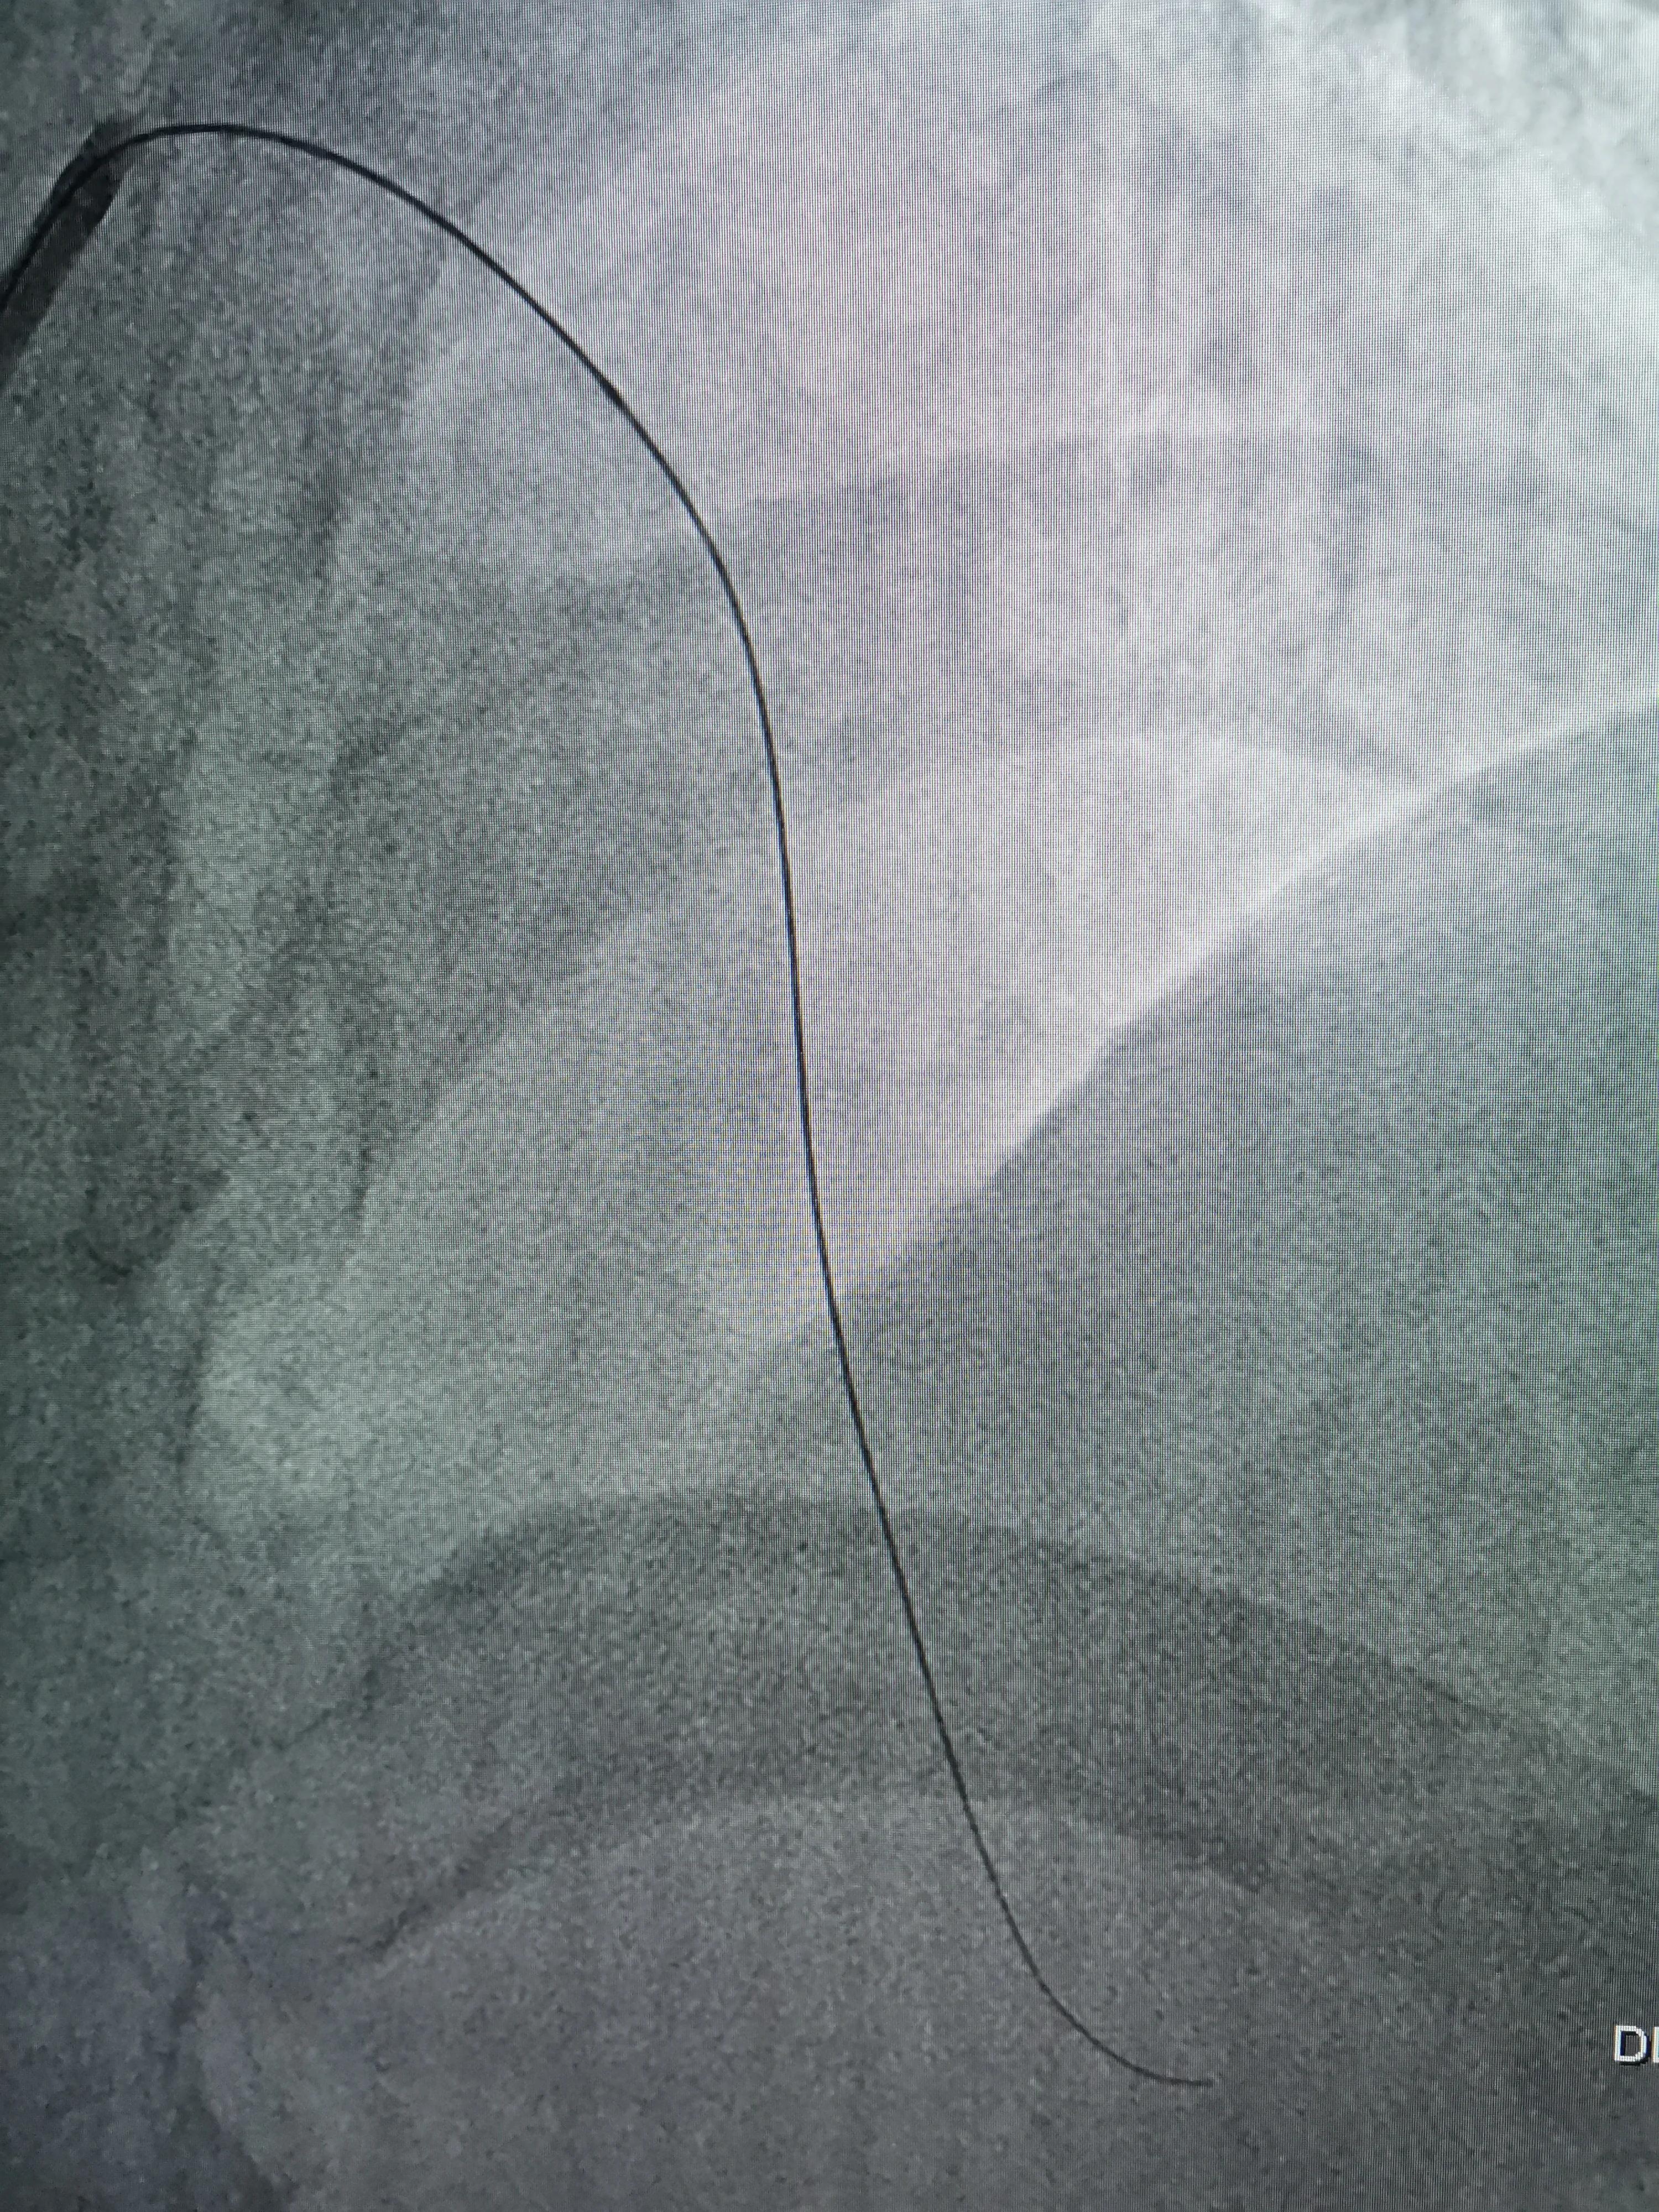

术前策略:次全闭塞病变,D1开口高度狭窄,且与主支有大于90度成角,导丝进入边支困难,先进导丝到LAD远端,扩张狭窄部位,再进导丝到D1远端保护。

(FielderXT导丝到LAD远端)